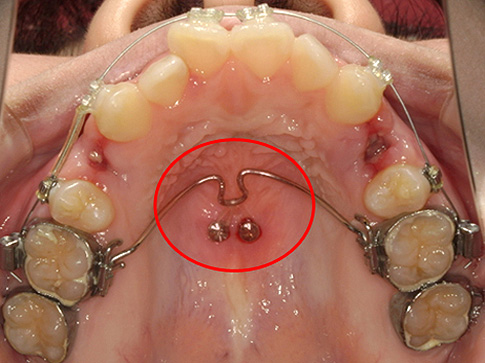

「歯科矯正用アンカースクリュー」と言う小さなスクリュー(ネジ)やプレートを写真のように歯ぐきの骨の部分に埋入し、歯を動かす時の固定源として用いる方法です。お子様の場合、固定源としてヘッドギア装置を使用しますが、時間的な制約が多い大人の方には歯科矯正用アンカースクリューを使用することが一般的になってきています。また歯の動きをより円滑にするために使用することもあります。

歯科矯正用アンカースクリューを使用すると、患者さんにヘッドギアなどのご自身で装置を装着してもらう必要が少なくなります。矯正用アンカースクリューは、チタン製の小さなネジのような器具で、骨の中に打ち込んで使用します。矯正用アンカースクリューが骨にしっかりと埋まっているため、アンカースクリューと歯を引っ張り合うと、骨に埋まっているアンカースクリューは動かず、歯のみを動かすことが可能です。

それにより、奥歯を前に動かさないように固定したり、反対に奥歯を前に動かしたい場合など、より治療計画通りに治療をすすめていくことが容易となりました。

歯科矯正用アンカースクリューはチタン製です。チタンは生体適合性に優れた金属で、骨折の接合や人工関節などにも用いられ、金属アレルギーの心配もほとんどない安全な素材です。サイズは植立する部位によっても異なりますが、直径約1.5mm,長さ約6mm程度のとても小さなサイズです。

専用の埋入器具を使用し、トルク(力のかけ具合)をコントロールしながら埋入を行います。

骨には痛覚がないため、基本的には痛みはありません。最初に歯茎はチクっと痛みを感じるため、その負担をなくすために局所麻酔を使用します。歯茎の表面だけに効けば良いので、麻酔の量自体もかなり少量です。痛みはなく外科的な侵襲は大きくありませんが、歯茎からネジのヘッド(頭の部分)が出てくるので多少の違和感は出てきます。

矯正用アンカースクリューは一定の割合で脱落すると報告されています。これは一般的なインプラントとは異なり、矯正が終わった際に撤去することが前提であるため、取り外しが可能なように埋入を行うためです。

何もしていなくても約1割ほどが脱落してしまうと報告もありますが、お口の中が不潔な状態でスクリュー周囲の歯茎が感染を起こしたり、手や舌で触っていると機械的なゆさぶりの力もあり、脱落リスクが高くなると言われています。